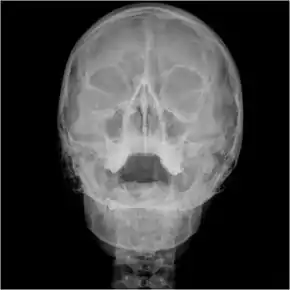

Orbital x-ray

Orbital x-ray or orbital radiography is an x-ray of both left and right eye sockets, to include the Frontal Sinuses and Maxillary Sinuses.

![]() Waters view showing diffuse prominent mucosal thickening in the right maxillary sinus and mild nmucosal thickening in the left maxillary sinus. | |

An orbital x-ray usually requires only one view unless the requester is looking for evidence of metallic fragments, in which case two projections can be made. One with the eyes looking up, one with the eyes looking down. These views will show any movement of fragments and helps rule out false positives / artefacts which may be present on the image receiver. Two other important views are the Water's view which helps visualise the anterior orbital floor and maxillary sinuses; and the Caldwell view which helps to visualise the frontal and ethmoid sinuses and posterior orbital floor.[3]